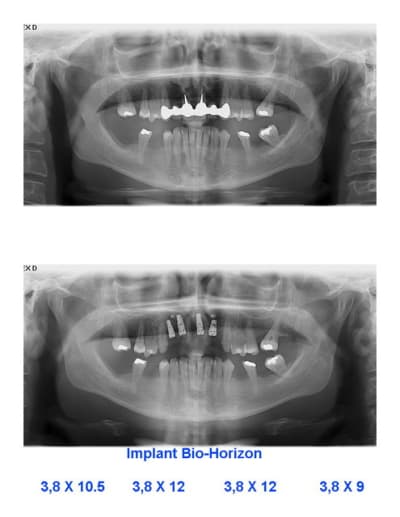

ce matin...

Patiente de 48 ans

Bridge mobile, dents 11 et 21 : perte osseuse +

11 sensible : fellure (sondage + en distal-palatin)

Plan de TX : dépose brige et implants...mais suite au scan...manque d'os en regard 12 et 22...donc greffe...

Pose 4 implants avec expansion 12 et 22

kit Messinger (merci pxav !)

Bon, pas parfait pour l'expansion, je ne suis qu'un débutant...alors, Mineros et membranne (ça je sais faire !)

De toute façon, faut bien remplir le vide en regard de 11 et 21...

Plus tard les implants en bas, mais au scan pas d'os...lame de couteau très, très mince.

pxav, si tu viens à Montréal, ce cas est pour toi !

Je ne suis pas encore certain de vouloir le faire...

Pour le choix de 4 implants, cela c'est fait durant la chirurgie...ma 1er idée étant exo + greffe (bloc d'os menton). J'ai enlevé 11 et 21, puis j'ai décidé de placer implants 11 et 21...ensuite j'aime pas faire bridge dents- implants et 2 implants en 11 et 21 pour 4 incisives...bof, alors j'ai sorti mon kit expansion (avec une pensée pour pxav), placer 12...et finalement 22...bref une intuition durant la chirurgie. J'avais tout mon temps. Total, incluant la dépose et la re-pose du bridge, l'anesthésie, les photos (pose à chaque fois...), radio : 2h45.

La patiente est très contente, éviter une greffe plus lourde, 4 implants avec possibilité de 4 couronnes individuelles et une seule chirurgie. De plus j+24h pas de douleur important, un peu d'enflure, mais tout va bien.